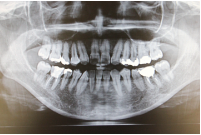

歯や顎の状態を詳細に診断できるデジタルレントゲンCTを完備し、より正確な治療計画を立てることが可能です。また、治療の痛みや不安を軽減するために電動麻酔を使用し、できるだけ負担の少ない治療を心がけています。進行した虫歯には「トライオート」を使用した精密根管治療を行います。徹底した感染対策のもと、患者様が安心して治療を受けられる環境を整えています。

インプラント治療をより安全かつ正確に行うために、歯科用CTやデジタルシミュレーションを導入しています。手術前のお口の中を徹底的に清潔にすることで「痛み」「腫れ」「感染」などのリスクを最小限に抑えた治療を実現します。

親知らず抜歯や、顎の痛み・口の開きづらさなどのお口周りのトラブルに対応いたします。レントゲンや歯科用CTによる的確な診断を行い、症状に合わせた適切な治療、必要に応じて連携医療機関にご紹介いたします。